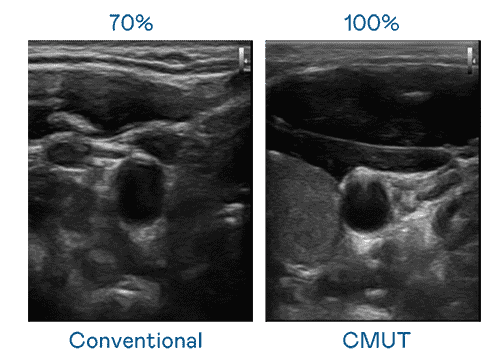

CMUT 技术是一种用电容式微机电元件来产生超音波讯号的技术。。与传统 PZT 压电式技术相比,,CMUT 频宽增加 30%,,更宽频的超音波讯号让影像解析度大幅提升,,是实现高影像品质医疗超音波扫描、、、促进精准医疗发展的关键技术。。。。

大频宽带来超清晰影像

超音波影像的解析度高低,,,首先取决于探头能发出的讯号频宽。。彩神vll CMUT 可提供高清晰的超音波讯号,,,,提供高频宽、、高灵敏度、、影像纹理细节更高的超音波影像,,协助医护人员缩短影像判读时间及利用精准的医疗影像进行诊断。。。。